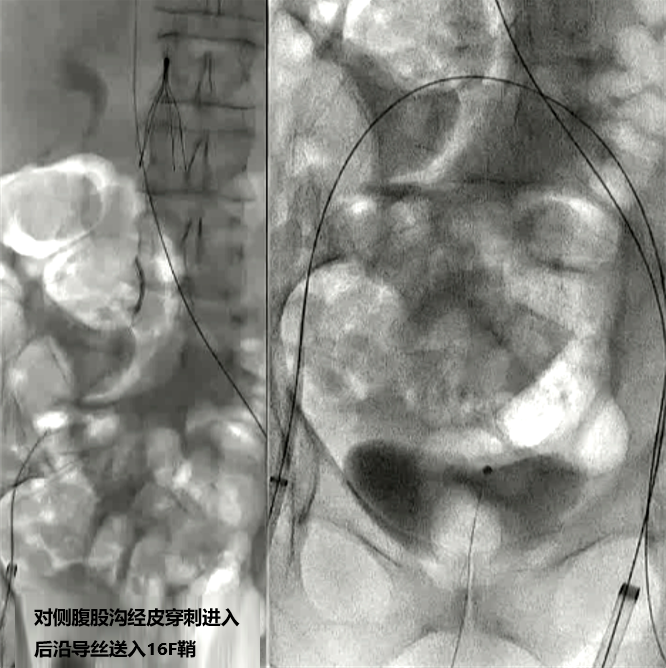

通过腘窝途径可处理同侧深部开口病变 经对侧途径进行深部/腘窝处操作

三、Penumbra Indigo 如何用于静脉血栓治疗?手术过程(简要):微创入路:

医生通过患者颈部、腹股沟或膝盖后侧的静脉经皮穿刺进入静脉靶血管。

建立通路:

在影像设备的引导下,将导丝和导管鞘送至血栓部位。